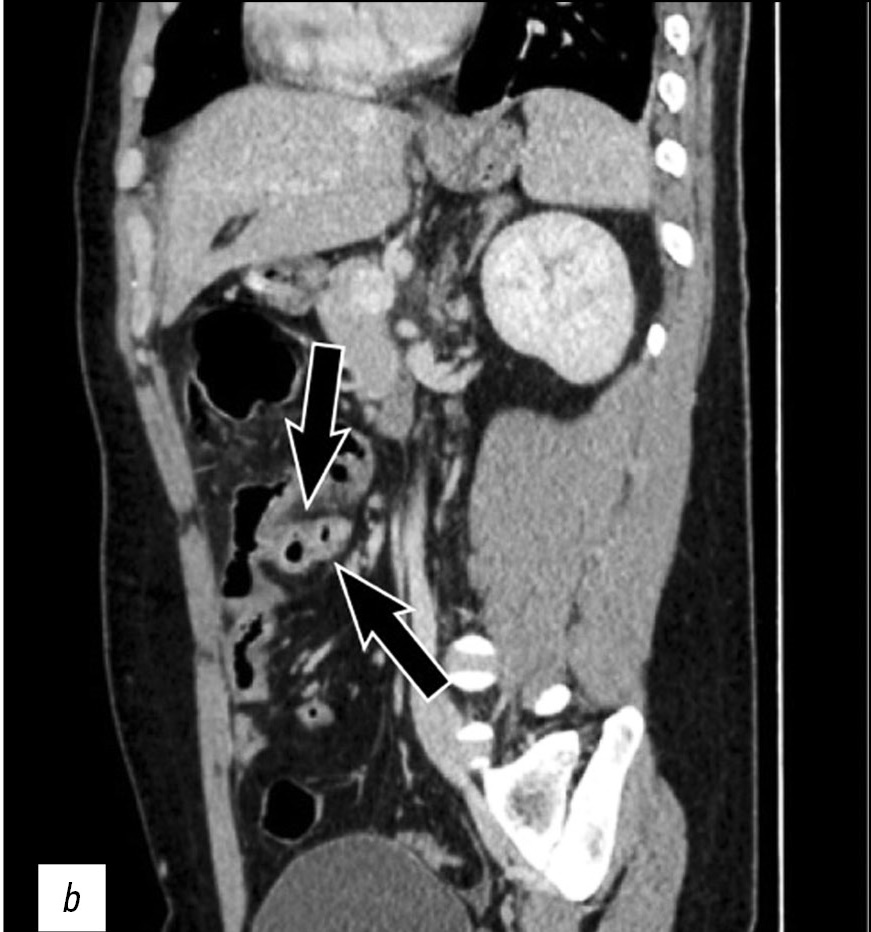

The case of a 26-year-old male patient with perforation of Meckel’s diverticulum, a rare complication of the most common congenital anomaly of the gastrointestinal tract, is reported in this article. This congenital condition can remain asymptomatic for a long time, and it can get complicated with diverticulitis, enteroliths, neoplasms, and rarely perforation, as in this case.

A preoperative radiological assessment is of fundamental importance for proper diagnostic and therapeutic management of the patient. In this article, we present the typical tomographic imaging features of this infrequent complication to assist radiologists in detecting it.

465-470